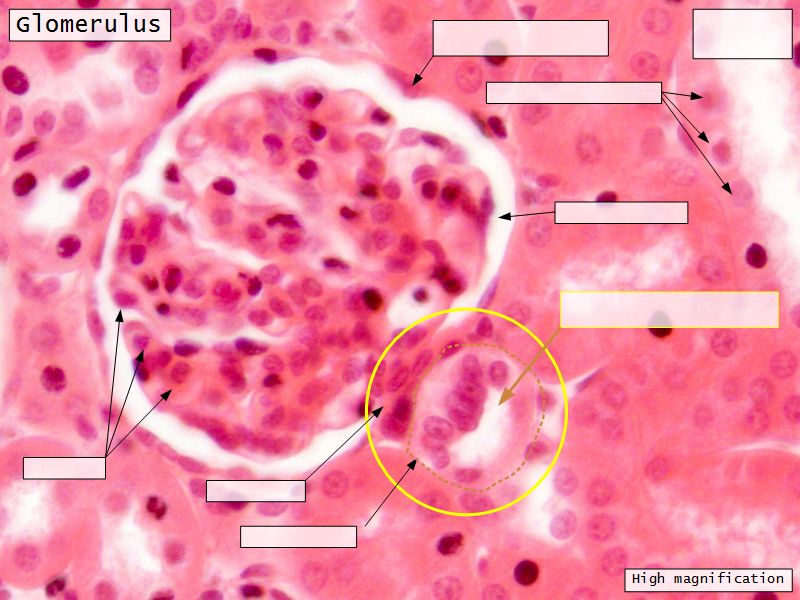

Renal corpuscle

- Tuft of capillaries

- grow into

- Blind end of nephron

- Several layers of epithelium

- Two sides

- Vascular pole

- Tubular pole

Epithelium layers

- Capillary endothelium

- Visceral layer of epithelium

- Podocytes

- Resting on glomerular basement membrane

- Capsular space

- Parietal layer of epithelium

- Simple squamous epithelium

Glomerular filtration barrier

- Three layers

- Fenestrated epithelium

- Exclude blood cells & platelets

- Glomerular basement membrane

- Main filtration barrier

- Thick

- Fused epithelial & endothelial BM

- Replenished by podocytes due to removal by mesangial cells

- Glomerular epithelium

- Through filtration slit

Capillaries

- Supported by

- Mesangial cells

- Mesangial matrix

- Phagocytic

- Maintain basement membrane

- Remove macromolecular deposits

Mesangial cells

- Around capillary loops at vascular pole

- Phagocytic

- Maintain basement membrane

- Remove macromolecular deposits

Podocytes

- Visceral layer of epithelium

- Protrude into capsular space

- Attached to basement membrane

- Long cytoplasmic extensions

- Primary processes

- Secondary processes

- Podocyte feet

- Tightly spaced

- Filtration slits 20 - 30 nm wide